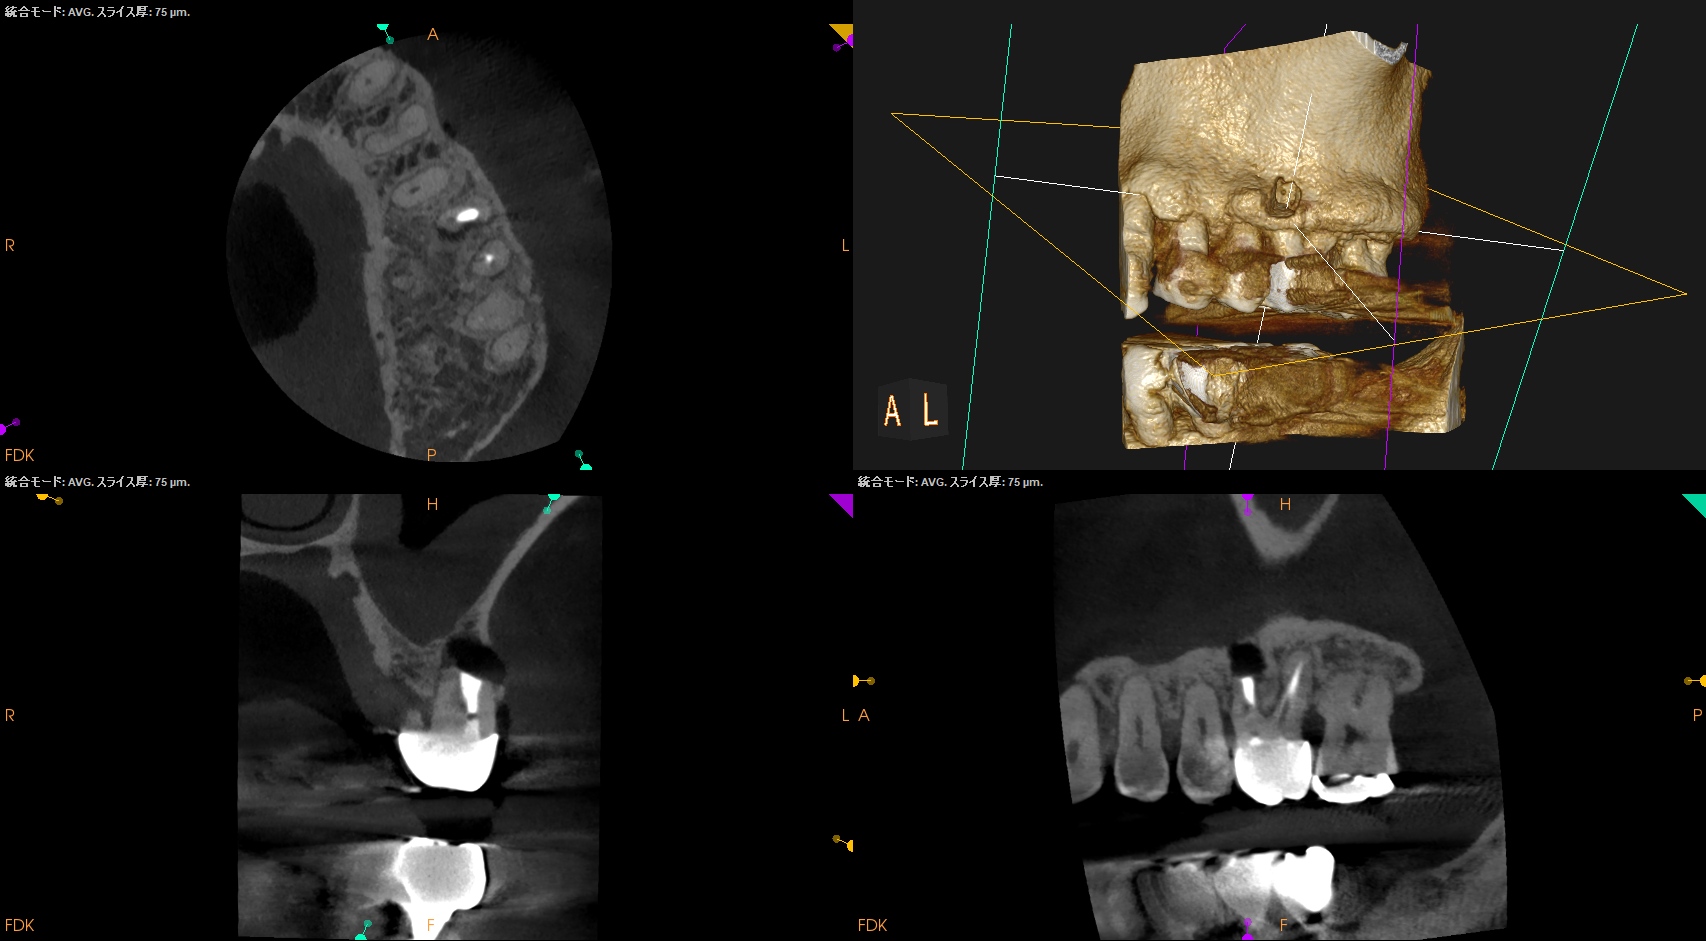

歯軸と並行になるようにCBCTのバーを動かした。

すると…

このような絵になる。

ここを、

こうすべきだろうか?

それともこのままで

いいだろうか?